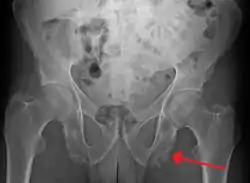

![]() اعتلال مرتكز العظم في الحوض ربما بسبب التهاب الفقار المقسط اعتلال مرتكز العظم في الحوض ربما بسبب التهاب الفقار المقسط | |